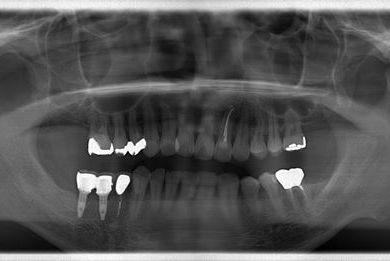

インプラントの症例写真 IMPLANT

インプラント治療+セラミック治療

| 性別/年齢 | 男性 / 36歳 | ||||||||||||||||||||||||||||||||

| 主訴 | インプラント治療と、その他全体的に歯の治療を希望。 | ||||||||||||||||||||||||||||||||

| 治療方針 | 欠損部分をインプラント治療にて、機能的・審美的回復を行う。 | ||||||||||||||||||||||||||||||||

| 治療内容 | インプラント2本、メタルボンドセラミッククラウン3本(メタルボンド用土台1本) | ||||||||||||||||||||||||||||||||

| 総治療費 | 629,685円 | ||||||||||||||||||||||||||||||||

| 治療期間 | 1年5ヶ月 |